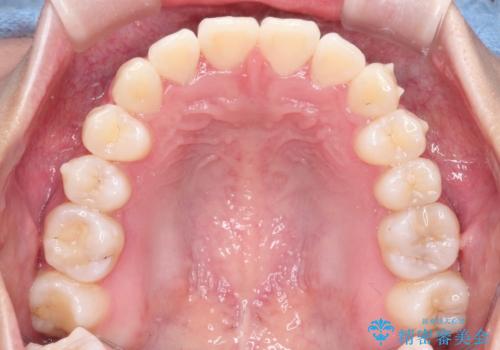

前歯のがたがたを綺麗にしたい

- 前歯がねじれていること、出ていることを主訴に来院されました。

前歯の突出感も改善され、満足していただきました。